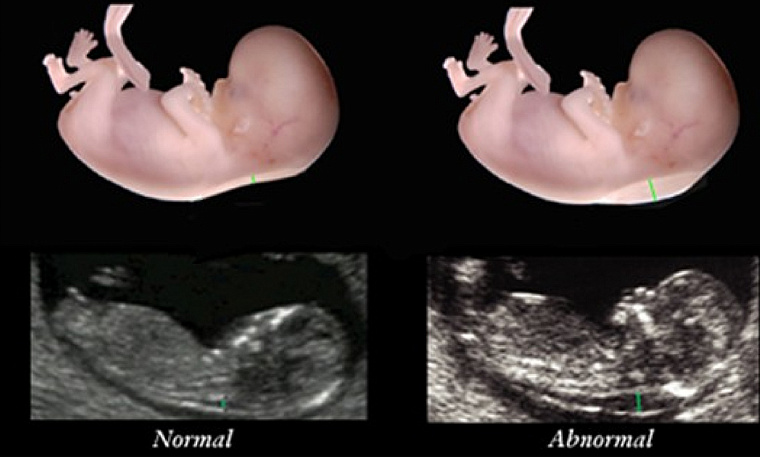

Состояние женщины, вынашивающей такого малыша, в общем и целом, не отличается от состояния любой другой беременной. Но анализы указывают на отклонения, потому что некоторые белки-маркеры вырабатывает сам плод, и они оказываются в крови женщины. К тому же, многое уже можно увидеть по УЗИ. Но диагноз не ставится, даётся только вероятность.

На первом скрининговом обследовании на 11-13 неделе беременности при наличии хорошего оборудования можно заподозрить патологию по укороченным костям бёдер и плеч, аномалиям развития сердца, недоразвитию костей носа, нехватке пупочной артерии и пр. Особенно важна толщина воротникового пространства и наличие носовой кости. Даже один обнаруженный симптом требует дополнительного обследования.

Второй скрининг на 16-18 неделе оценивает очень подробно внешний вид плода в различных проекциях. Анализ крови - теперь «тройной тест» (ХГЧ, альфафетопротеин, свободный экстрадиол). Повышение или понижение показателей относительно нормы говорит о нарушениях работы нервной трубки или хромосомных патологиях.